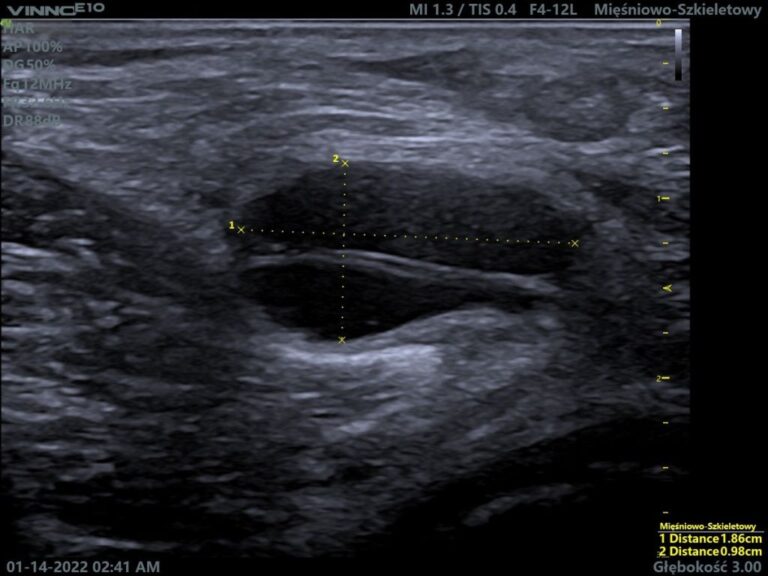

Torbiel Bakera jest to wypełniona płynem stawowym przestrzeń, zlokalizowana w dole podkolanowych, między głową przyśrodkową mięśnia brzuchatego łydki, a mięśniem półbłoniastym. Po raz pierwszy została opisana przez brytyjskiego chirurga Williama Morranta Bakera. Torbiel można wyczuć palpacyjnie jako guz pod kolanem. Do szczegółowego zdiagnozowania konieczne jest wykonanie badania USG.

W zależności od przyczyny, torbiel może różnić się budową ścian. Wyróżniamy torbiele podkolanowe:

- włókniste – mają ścianę o grubości 1-2 mm , dobrze zarysowaną i odgraniczoną . Posiadają też gładką, błyszczącą powierzchnię wewnętrzną, zbudowaną z tkanki włóknistej. Mogą tworzyć się w nich ciała ryżowate.

- synowialne – mniej odgraniczone od otaczających tkanek. Posiadają grubą na 2-5 mm ścianę, mniej błyszczącą, z tworami kosmkowymi. Ściany zbudowane są z tkanki łącznej włóknistej mniej gęstej, która pokryta jest komórkami o sześciennym kształcie.

- zapalne – są otoczone grubą, 8 milimetrową ścianą, o strukturze „ kudłatej” od pokrywających ją wypustek. W ścianie znajdują się m.in. limfocyty oraz komórki wielojądrowe. W tym rodzaju torbieli, mogą tworzyć się chrzęstno- i kostno-podobne elementy.